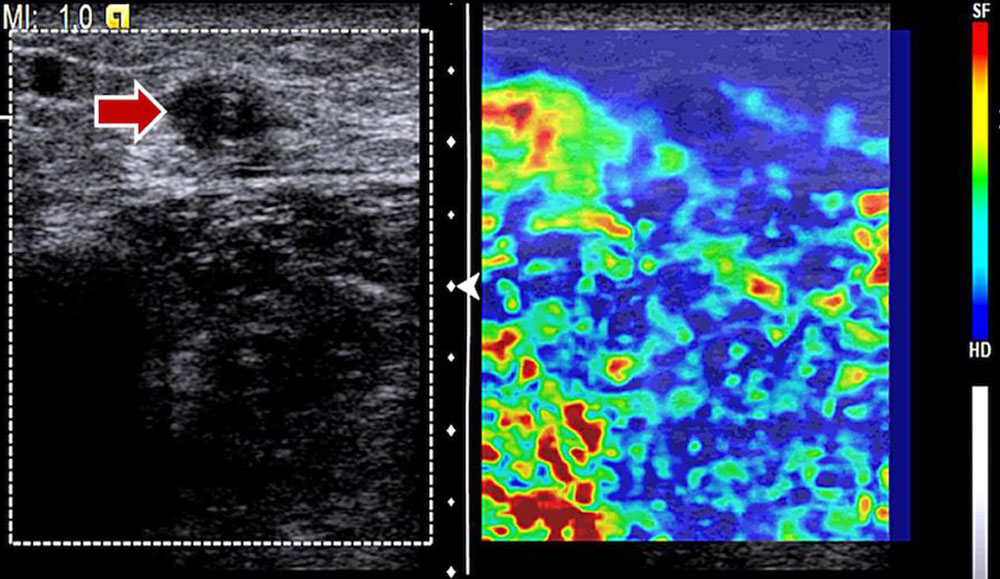

Ultrasound elastography allows for imaging of the hardness / softness of a tissue in color.

ElastographyColor-coded imaging of tissue hardness/softnessDifferentiation of therapy-induced effects, differential diagnosis

• Lymphatic malformation: In B-mode ultrasound, macrocystic lymphatic malformations appear as echo-free cysts with a thin wall and possibly septa. Blood vessels in the septa and cyst walls are occasionally identifiable. In contrast to venous malformations, macrocystic lymphatic malformations are not as compressible and rather elastic. Microcystic lymphatic malformations show a very heterogeneous ultrasound pattern. In addition to small echo-free microcysts, hypoechoic and hyperechoic masses can also be detected. The cysts themselves do not enhance contrast medium in CEUS. There is no flow on CCDS.